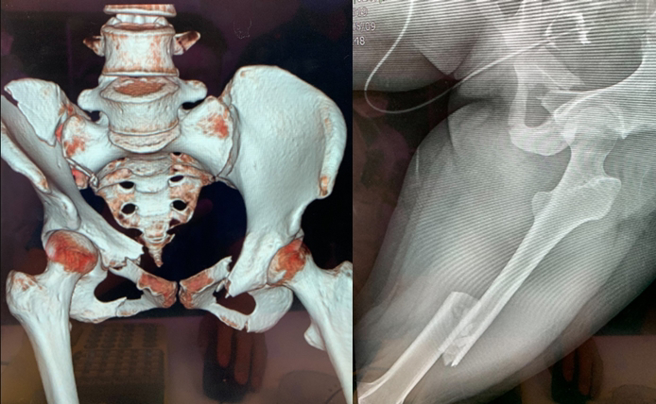

透過X光片可見,受害女子因遭車子輾過,骨盆變形外還骨折,傷勢十分嚴重。(翻攝自Dcard)

受害女子的姊姊曝光的驗傷單寫道,妹妹的臉、肩膀、手臂、背部、腰部與臀部等處都有挫傷,骨盆與左下肢變形,還有多處骨折等,傷勢十分嚴重,每個手術都需高昂的醫藥費,還須面對妹妹恐下半身癱瘓的最壞打算,家人為此都承受巨大心理壓力。